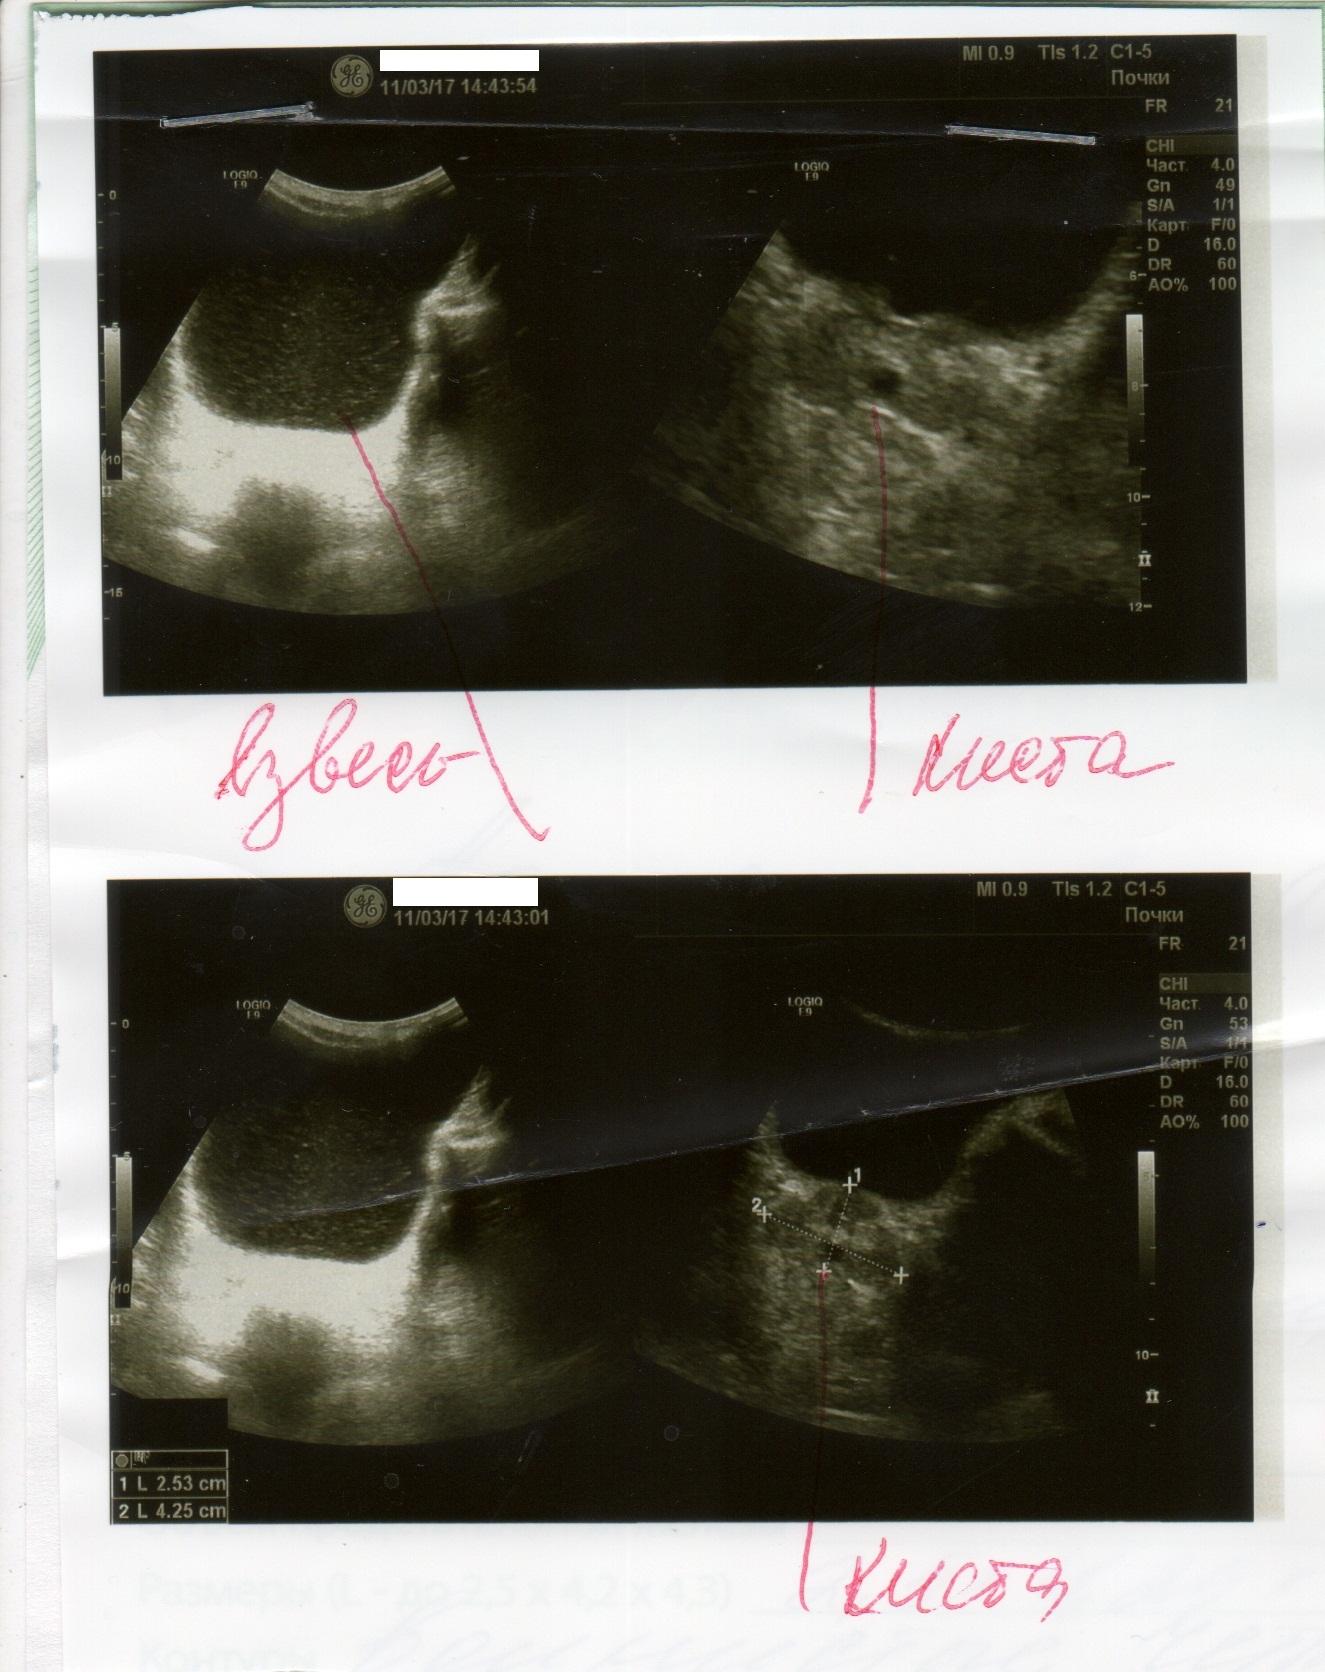

Здравствуйте. Мне 29 лет. Вес 60 кг. Рост 174см. Пол мужской. Беспокоят частые позывы к мочеиспусканию уже где-то пол года. От 6-8 раз в сутки. Раньше столько не ходил. Чувствую что мочевой пузырь не совсем полный. Где то 100-150мл и бегаю в туалет. Очень давно при прыжках с небольшой высоты была резкая боль в промежности. Сейчас очень редко бывает, не знаю простата это болит или что-то другое. Ночью встаю 1 раз. Струя нормальная. Делал УЗИ несколько раз. Врач пальцем проверил простату, сказал, что с левой стороны прощупываются неровности. Боли при ощупывании не было, было чувство на головке, как будто позыв к мочеиспусканию сильный. Сразу ершиком взял анализ ПЦР на инфекции. Нашли только гарднерелла. Сразу начал выписывать антибиотик. Я сказал, не лучше будет на чувствительность сделать анализ. Сказал, зачем терять время. У меня во вложении назначение, ответы анализа, УЗИ.

5. Из клиники только частые позывы. Есть какие то изменения в простате по УЗИ, но я до сих пор сомневаюсь есть ли у меня хр. простатит и какой именно(синдром тазовой боли, инфекционный и др.). Что еще нужно сделать, чтобы определиться с причиной частых позывов?